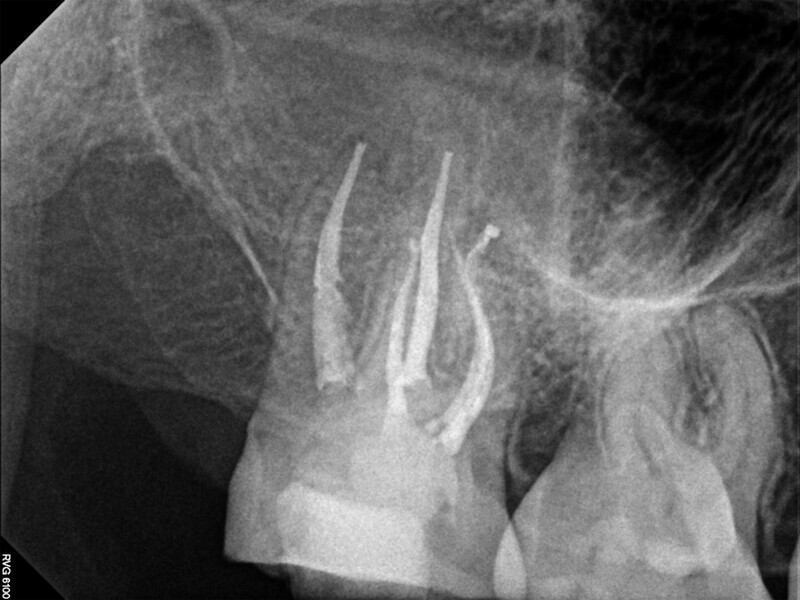

Fig. 3: Calcium hydroxide extruded into the mandibular canal through a perforation.